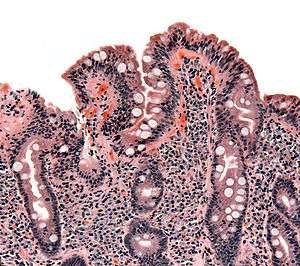

Whipple's disease: Alcian blue with apparently eosin counterstain enlarged villus with many macrophages

Biopsy of small bowel showing coeliac disease manifested by blunting of villi, crypt hyperplasia, and lymphocyte infiltration of crypts.